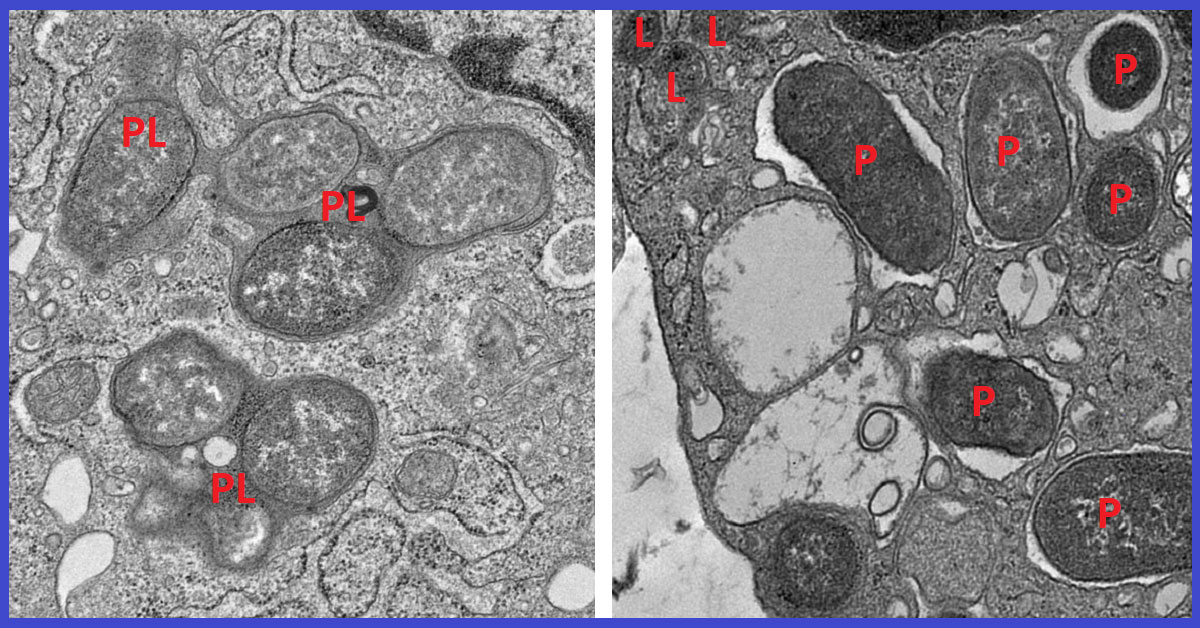

Using a powerful machine learning tool, the researchers analyzed thousands of macrophage gene expression patterns from colon tissue affected by IBD and from healthy colon tissue. They identified a macrophage gene signature consisting of 53 genes that reliably separates reactive, inflammatory macrophages from tissue-healing macrophages.

One of these 53 genes encodes a protein called girdin. Further analysis revealed that in non-inflammatory macrophages, a specific region of the NOD2 protein binds to girdin. This suppresses runaway inflammation, clears harmful microbes, and allows for the repair of tissues damaged by IBD. But the most common Crohn’s disease mutation to the NOD2 gene deletes the section of the gene that girdin would normally bind to. This results in a dangerous imbalance between inflammatory and non-inflammatory macrophages.

The researchers then confirmed the importance of the interaction between NOD2 and girdin by comparing mouse models of Crohn’s disease lacking the girdin protein to those with girdin intact. They found that mice without girdin suffered an imbalance in their gut microbiome and developed inflammation of the small intestine. They often died of sepsis, a condition in which the immune system mounts an excessive response to an infection, causing inflammation throughout the body and damage to vital organs.